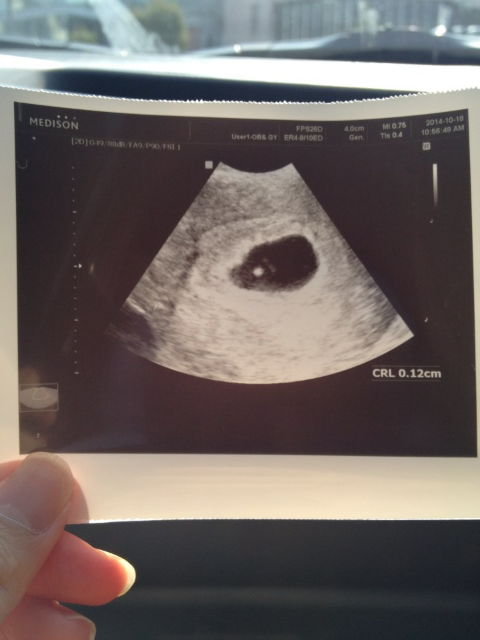

시작은 점이었다.

친한 언니와 진하게 마시고 온 마늘이 몸이 좀 이상하다고 했고 결과는 두 줄이었다.

7시 48분. 3.36k에 53cm였다.